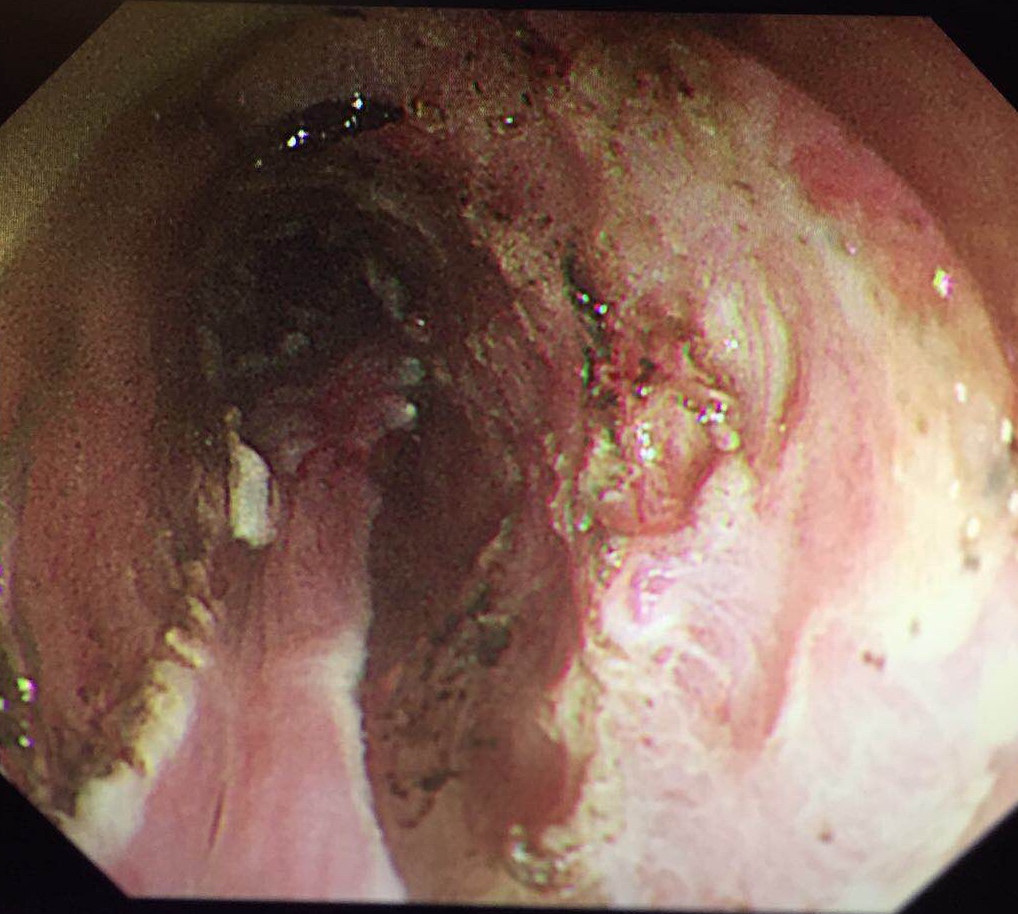

4月20日,第二届北京协和医院—福建省立医院消化内镜合作共建学术会议在北京协和医院召开。我院消化内镜中心梁纬主任带领14人的团队参加会议,邓万银副主任医师作手术演示。浙江大学附属第一医院许国强副院长,北京协和医院消化内科吴晰副教授、冯云路博士分别就《环形超声扫描操作技巧》《纵轴超声扫描技巧》《小探头操作技巧》作主题演讲。

与此同时,北京协和消化疾病及消化内镜国际论坛暨第25届北京协和医院消化疾病与消化内镜研讨会在北京举行,国内外五十余位专家、五百余位代表参会。梁玮主任受邀作手术演示,完美演绎了一例病灶长达200px近环周的高难度早期食管癌“梁式ESD”治疗,向国内外同仁展示出精湛、创新的福建消化内镜技术,赢来阵阵喝彩。